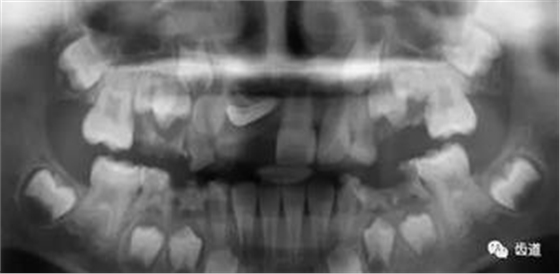

三)種植修復(fù)

CBCT在牙種植修復(fù)中的應(yīng)用。種植前利用CBCT對患者的牙床進(jìn)行檢查,可精準(zhǔn)判斷牙槽骨的寬度、厚度及高度、骨的密度、重要的顏面神經(jīng)、血管和鼻竇位置等。臨床醫(yī)生不僅可以在計(jì)算機(jī)直觀的看到牙槽骨的立體影像,還可以切換不同的視角來觀察硬組織之間的位置關(guān)系,在手術(shù)方案中避開危險(xiǎn)區(qū)域,保證手術(shù)的安全性。臨床醫(yī)生還可以利用CT數(shù)據(jù)進(jìn)行數(shù)字模型重建,配合軟件預(yù)先做好手術(shù)模板,使種植手術(shù)更安全快捷,避免在種植手術(shù)過程中不慎破壞神經(jīng)、鼻竇等解剖結(jié)構(gòu),導(dǎo)致顏面神經(jīng)麻痹、鼻竇炎等并發(fā)癥的發(fā)生。

1、下頜骨種植牙前測量準(zhǔn)備影像

2、上頜骨種植牙前準(zhǔn)備影像

3、下頜骨種植牙術(shù)后